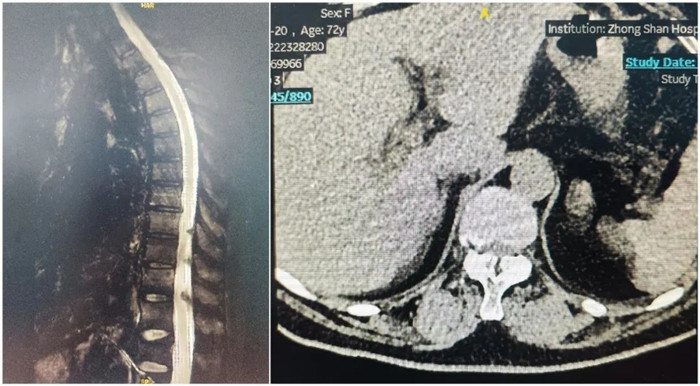

患者一個月前因雙側下肢疼痛至醫院就診,診斷為腰椎間盤突出?;颊咦孕兄猎\所就診,予以推拿牽引術,疼痛未明顯緩解,到醫院進一步治療。影像診斷:L3-4椎間盤突出,椎管變窄(中央型)。

術前影像

使用普愛醫療術中三維導航C臂進行透視,根據透視影像引導確認責任間盤、規劃手術方案,充分暴露骨組織,并通過專業器械切除椎板,暴露神經及椎管;在C形臂的引導下,確定責任間盤上下椎體椎弓根位置,制定進針點及進針方向,沿椎弓根方向植入脊柱螺釘進行固定;放入椎間融合器,加固螺釘。最后再進行C形臂透視,確認手術的完成效果。